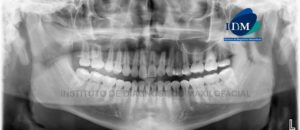

Paciente masculino de 56 años de edad acude al Instituto de Diagnóstico Maxilofacial por molestia en zona molar de lado izquierdo. A la evaluación panorámica